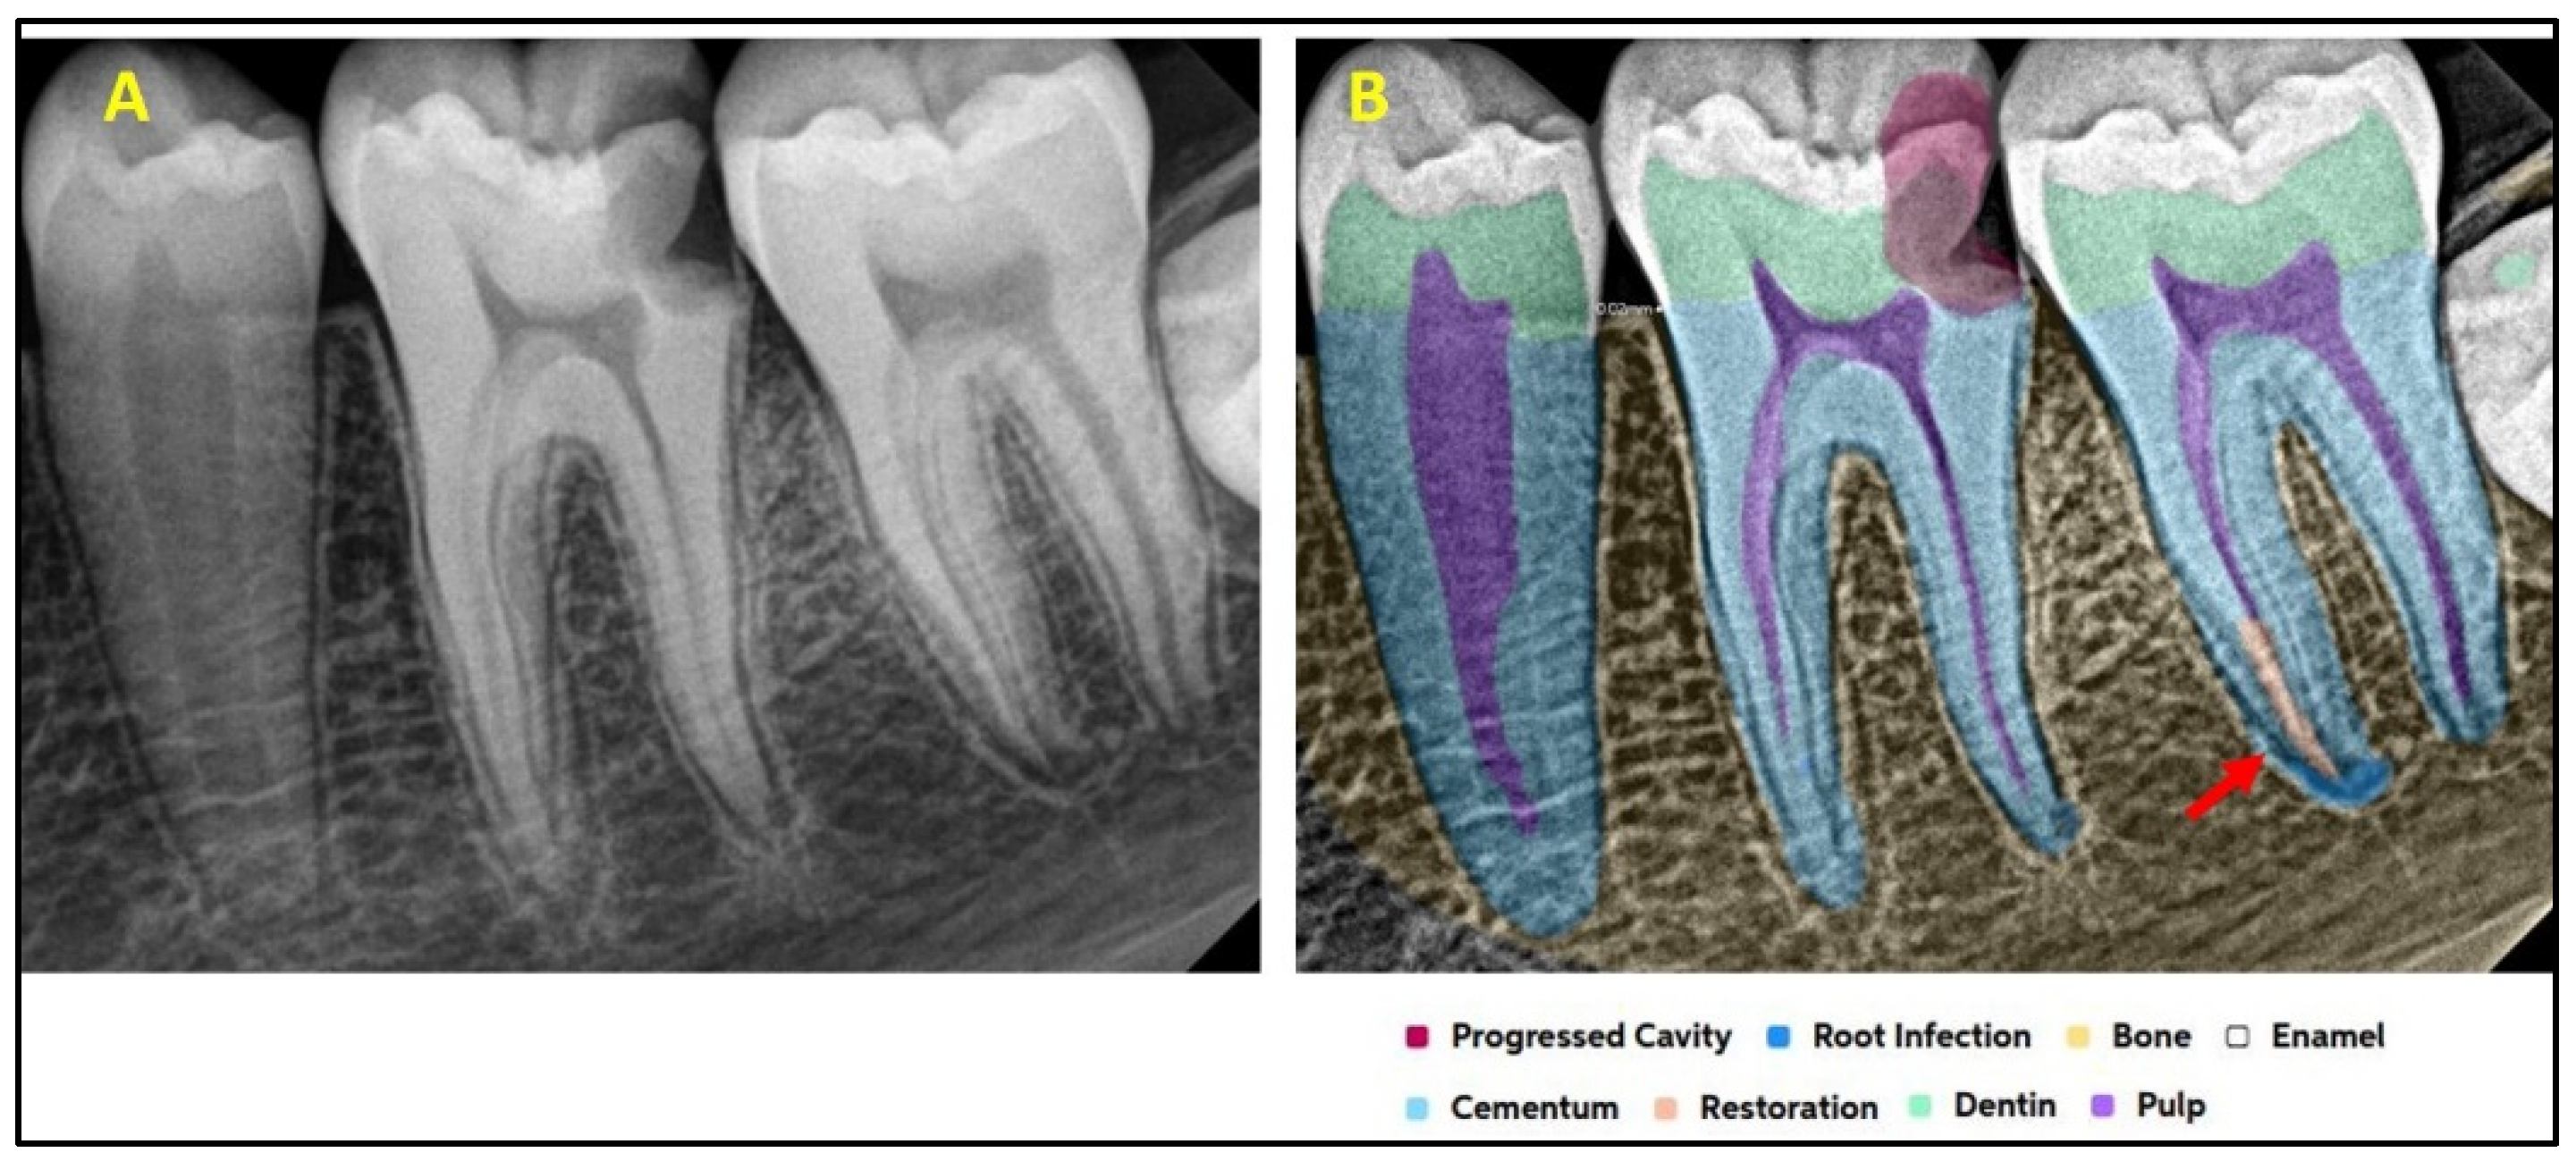

2.2. AI Software Architecture